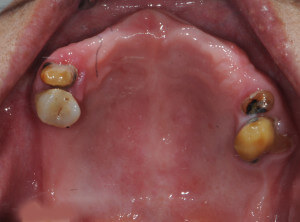

婆婆剛來的時候口腔狀況很差,長期配戴的活動假牙早已經鬆動不合,口內僅存的幾顆牙齒也岌岌可危

婆婆很節省,一直說年紀大了,不用花大錢做牙齒,唯一的希望就是可以吃個銅鑼燒.幫她檢查了剩餘的牙齒,因為牙周病與蛀牙的緣故,口內的牙齒必須全部拔除.在有限的預算裡,我們只能用製作全口假牙去恢復咬合功能.